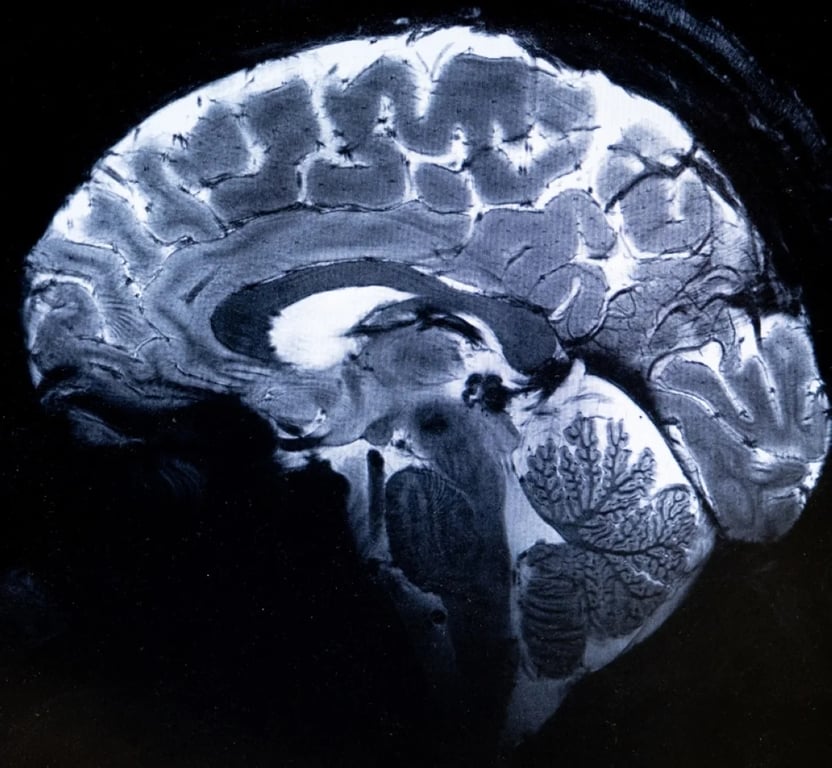

Перше деталізоване зображення людського мозку

Детальне зображення людського мозку на апараті Iseult. Авторство: CEA

Як розповів фізик, який працює над цим проєктом, Александр Віньо, за допомогою цієї машини можна побачити крихітні судини, які живлять кору головного мозку або деталі мозочка, які досі були майже невидимі.

Однією з головних цілей такого потужного сканера є уточнення нашого розуміння анатомії мозку та того, які зони активуються, коли він виконує певні завдання.